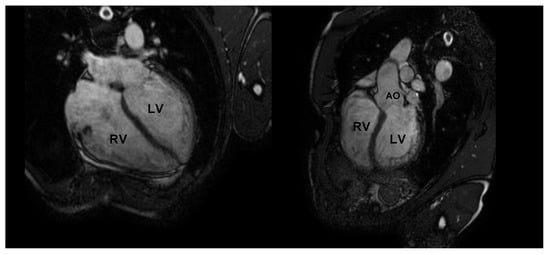

The physiological hypertrophy of athlete’s heart is characterized by a harmonic and symmetric wall thickening that is homogeneously distributed and involves all the cardiac chambers (Figure 1). The exercise-induced chamber thickening is proportional to the type of sport participated (mainly in combined power and endurance disciplines) and it is reversible after temporary (3 months) detraining [10]. A physiological enlargement of both ventricles is usually observed (mostly among endurance athletes), together with a proportional atrial enlargement [11,12,13,14,15,16]. Despite the cardiac chambers’ hypertrophy and enlargement, cardiac systolic function is not altered in athletes, with no significant differences compared to untrained subjects [12,17,18,19]. Likewise, LV diastolic function is normal and an increased contribution of early filling velocity at rest (E/A > 2) can be observed [20,21,22,23,24]. Finally, aortic root diameters are, generally, normal in athletes [25,26,27].

Figure 1.

Standard echocardiography in an endurance athlete (cyclist). The physiological hypertrophy of the athlete’s heart is characterized by harmonic and symmetric wall thickening which is homogeneously distributed and involves all the cardiac chambers. In parasternal long-axis (top left), short-axis (top right), apical 4-chamber (bottom left), and subcostal (bottom right) views, both left and right chamber dilatation is evident. LV: left ventricle; RV: right ventricle.